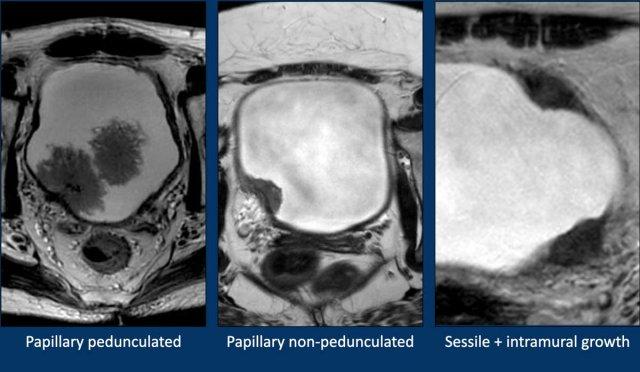

Có ba loại khối u bàng quang:

- Khối u dạng nhú phát triển vào lòng bàng quang, có hoặc không có cuống khối u. Cuống khối u được đặc trưng bởi giảm tín hiệu trên chuỗi xung T2W và DWI, trong khi tăng tín hiệu trên chuỗi xung DCE.

- Khối u phẳng nông hay ung thư biểu mô tại chỗ, được giới hạn trong lớp niêm mạc và không lan qua các lớp khác.

- Ung thư biểu mô phẳng xâm lấn hay khối u dạng không cuống với sự phát triển trong thành bàng quang.

Dưới đây là ba ví dụ trên MRI:

- Khối u dạng nhú có cuống.

- Khối u dạng nhú không có cuống.